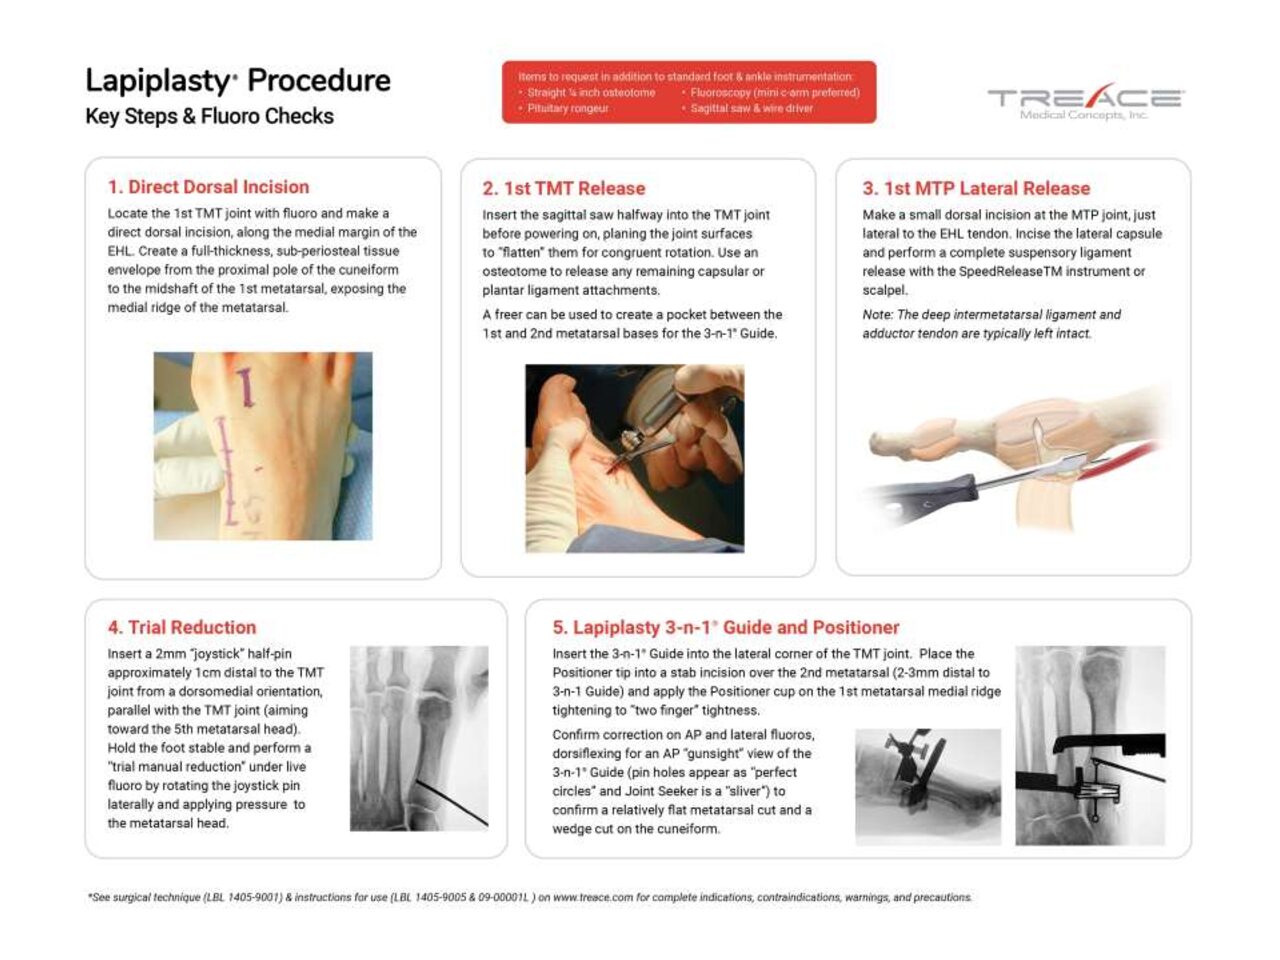

Key Surgical Steps

How the Lapiplasty® Procedure Works

1. Correct

Make Your Correction Before You Cut

The Lapiplasty® Positioner is engineered to quickly and reproducibly correct the alignment in all three planes, establishing and holding true anatomic alignment of the metatarsal and sesamoids.1

2. Cut

Perform Precision Cuts with Confidence

The Lapiplasty® Cut Guide delivers precise cuts with the metatarsal held in the corrected positions, ensuring optimal cut trajectory with only 2.4-3.1mm average metatarsal shortening.3

3. Compress

Achieve Controlled Compression of Joint Surfaces

The Lapiplasty® Compressor is designed to deliver controlled compression4 to the precision-cut joint surfaces, while maintaining 3-plane correction.

4. Fixate

Apply Multiplanar Fixation for Robust Stability

Low-profile Biplanar Plating provides biomechanically-tested5,6 multiplanar stability for rapid return to weight-bearing in a boot.1